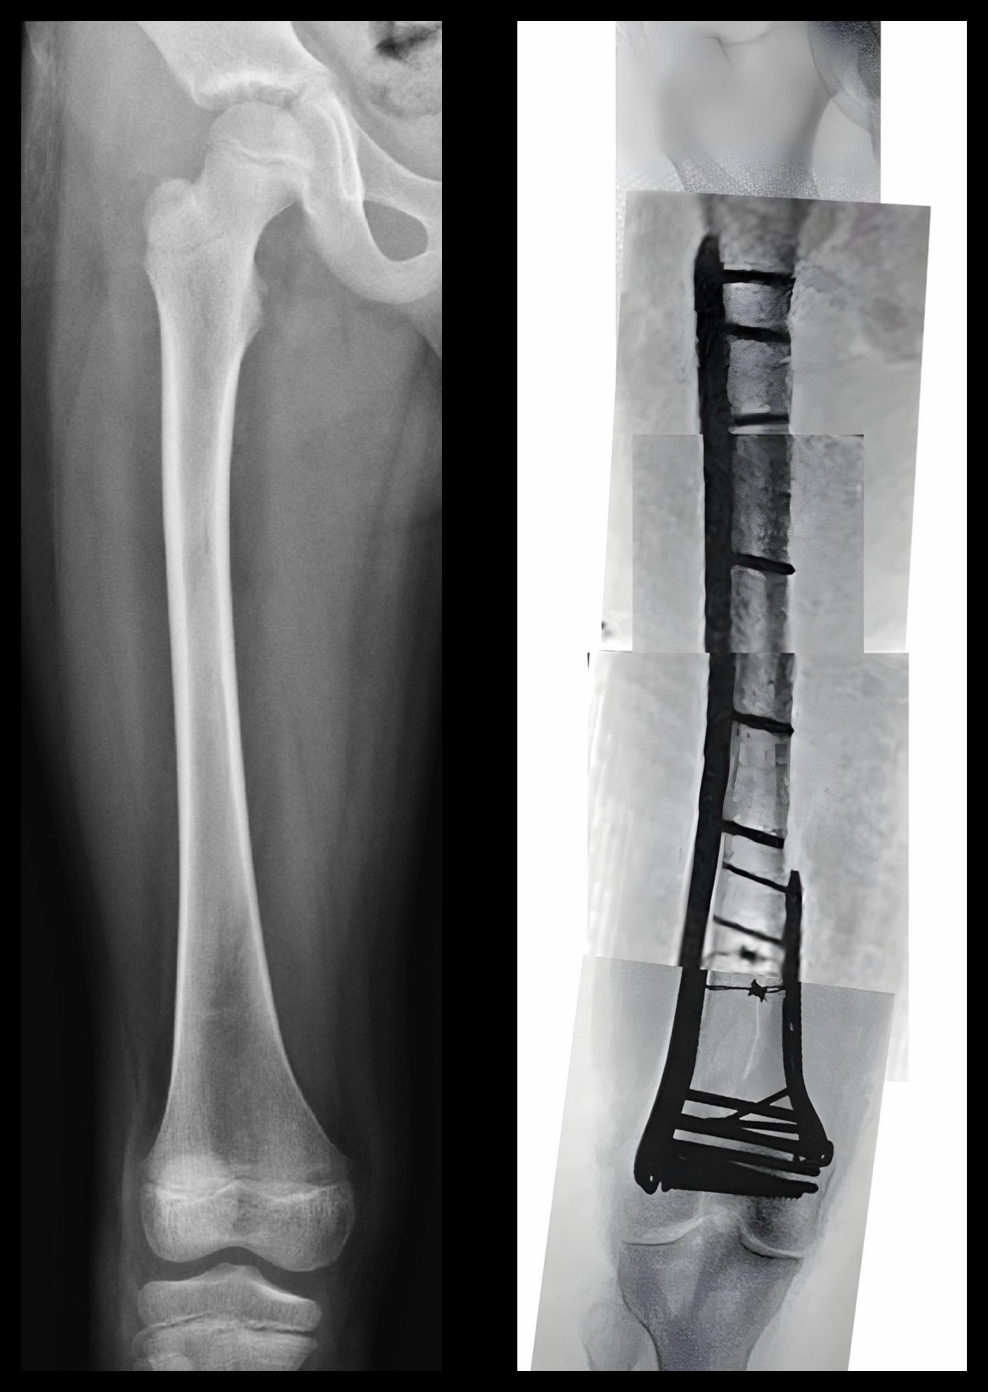

Femur Fracture with Rod in Place Musculoskeletal Case Studies Titanium Femur Rod Weight Im rods are inserted into the bone marrow canal in the center of the long bones of the extremities. This surgical procedure stabilizes severe fractures of the femur by placing a metal rod into the center of the femur. They are also called intramedullary nails. 2023 i had a total knee replacement. Here’s a reference table for steel rod weight. Titanium Femur Rod Weight.

Titanium Femur Rod Weight . Recovery was difficult and the best bend i ever attained was 102. They are also called intramedullary nails. The weight of a titanium femur rod will be different depending on the length and diameter of rod needed by the patient. The patient is positioned so that the side of the thigh is clearly visible to the. 2023 i had a total knee replacement. Rods and nails are long cylinders that are made of surgical grade metal (stainless steel or titanium). This surgical procedure stabilizes severe fractures of the femur by placing a metal rod into the center of the femur. They may be used in the femur (thigh bone) or tibia (shin bone), for example. Im rods are inserted into the bone marrow canal in the center of the long bones of the extremities. Intramedullary (im) rods are used to align and stabilize fractures. Here’s a reference table for steel rod weight based on diameter, with approximate weights per foot and meter. They are also called intramedullary (im) devices, as they go inside of the bone. Steel rods are commonly used. One of the main reasons a patient might need an artificial femur—called a “total femur” in the medical industry—isn’t a traumatic accident: These devices are inserted inside the marrow cavity of a long bone (tibia, femur, humerus, or forearm bones).

Titanium Femur Rod Weight Intramedullary (im) rods are used to align and stabilize fractures. Recovery was difficult and the best bend i ever attained was 102. They may be used in the femur (thigh bone) or tibia (shin bone), for example. Steel rods are commonly used. One of the main reasons a patient might need an artificial femur—called a “total femur” in the medical industry—isn’t a traumatic accident: Im rods are inserted into the bone marrow canal in the center of the long bones of the extremities. The weight of a titanium femur rod will be different depending on the length and diameter of rod needed by the patient. They are also called intramedullary (im) devices, as they go inside of the bone. Here’s a reference table for steel rod weight based on diameter, with approximate weights per foot and meter. 2023 i had a total knee replacement. These devices are inserted inside the marrow cavity of a long bone (tibia, femur, humerus, or forearm bones). The patient is positioned so that the side of the thigh is clearly visible to the. They are also called intramedullary nails. Rods and nails are long cylinders that are made of surgical grade metal (stainless steel or titanium). This surgical procedure stabilizes severe fractures of the femur by placing a metal rod into the center of the femur. Intramedullary (im) rods are used to align and stabilize fractures.